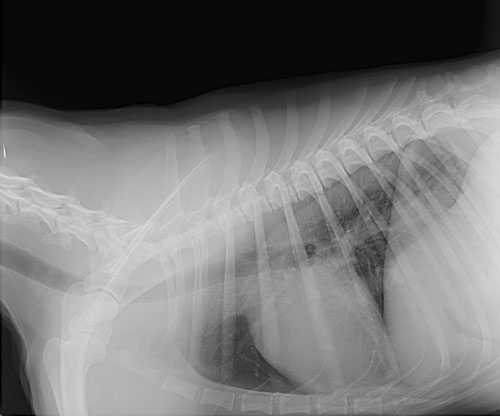

• X-rays: Mainly used to assess broken bones, this common test also allows veterinarians to see foreign objects in the body as well as some tumors.

Pet X-Ray